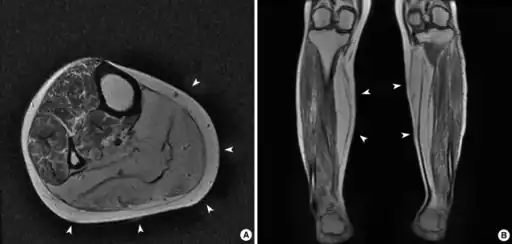

![]() |